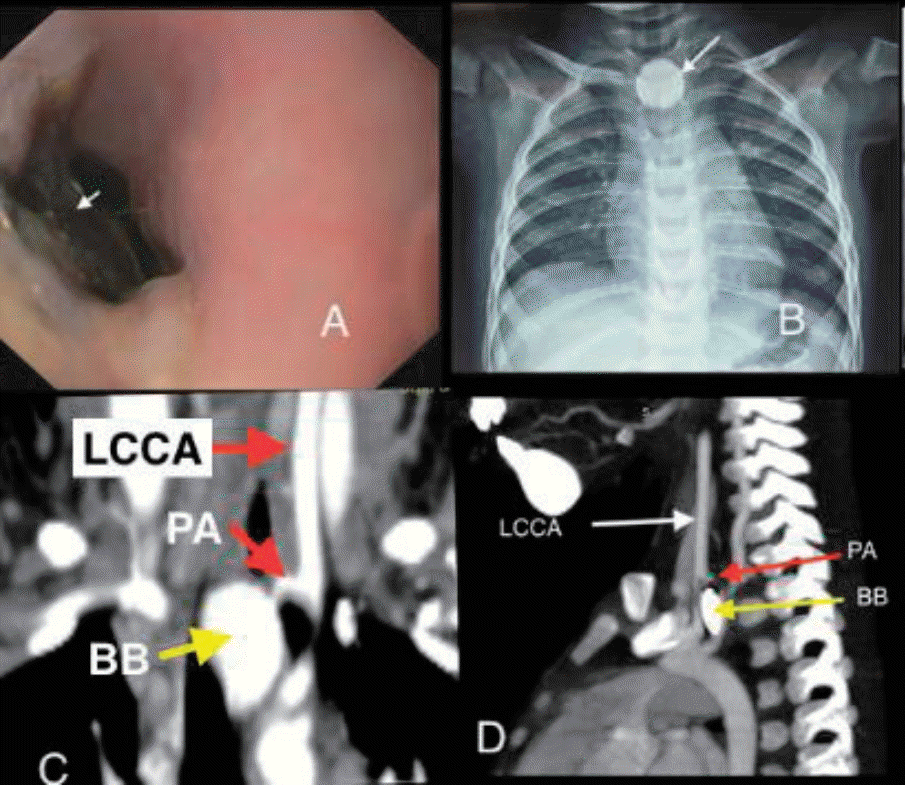

A previously well 18-month-old boy presented with 16 days history of poor feeding, fever and 2 episodes of clinically significant, well compensated upper gastrointestinal bleeding (UGIB) in the form of hematemesis and melena on day 10 and day 14 of illness respectively. He was transfused 2 units of packed red blood cells (PRBCs) elsewhere before presenting to us. On examination, the child was irritable, severely pale and had no splenomegaly. There was no history of witnessed foreign body ingestion. An urgent upper gastrointestinal endoscopy was performed after hemodynamic resuscitation which revealed an impacted foreign body in the upper esophagus with surrounding ulcerated mucosa (Fig. 1A). X-ray showed envisioned halo sign suggestive of BB (Fig. 1B). Computed tomography angiography (CTA) showed proximal left common carotid artery (CCA) pseudoaneurysm (4.9 mm×4 mm) in close proximity to BB suggestive of vascular fistula (Fig. 1C and D). Surgical consult was sought and BB removal was planned in operation theatre (OT) with cardiovascular and thoracic surgery back-up. Meanwhile, the child had another bout of massive UGIB requiring PRBC transfusions. After stabilization, the child was taken to OT and exploration was done via median sternotomy incision. Intraoperative findings included impacted BB in cervical esophagus and inflamed esophagus densely adhered to pretracheal fascia, left carotid sheath and prevertebral fascia. Intraoperative bleeding was seen at level of CCA, vascular control was ensured by using running sutures. BB was retrieved by intraoperative endoscopy by using grasping forceps. It was a lithium BB (20 mm×20 mm) (Fig. 2A). Esophagectomy with cervical esophagostomy, decompressive gastrostomy and feeding jejunostomy were done. Following surgery, feeding was established via jejunostomy. However, the child had right hemiparesis. CTA-head showed infarct in left parieto-temporal region involving middle and anterior cerebral artery territory (Fig. 2B and C). It was attributed to intraoperative compromised cerebral circulation due to probable clamping of branch of CCA while ensuring vascular control. Postoperative, child had fever, so antibiotics were upgraded from first-line (cefotaxime, amikacin and metronidazole) to piperacillin-tazobactum and teicoplanin. Blood culture grew Enterococcus fecalis sensitive to teicoplanin and child responded. Fortunately, hemiparesis has improved over the next one month and the child is on full enteral feeds and has a plan to restore anatomy after 3 months.

(A) Retrieved button battery (20 mm×20 mm). (B and C) Computed tomography image of the head showing a left parietotemporal infarct (white arrow).